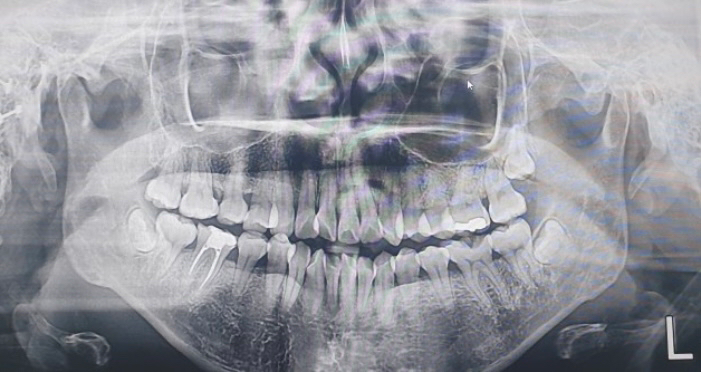

매복된 사랑니 뽑아야 하나요??

정면 기준으로 오른쪽 위와 양쪽 아래 두곳에 사랑니가 나는데 의사쌤이 매복된거라 안뽑아도 된다고 하는데 맞나요? 매복된거도 나중에 신경건들거나 앞니를 건들거나 움직여서 빼는게 좋다고 저희 언니는 그래서 뺏거든요 저는 언니가 간 치과랑은 다른 치과인데 냅둬도 된다고 하니 뭐가 맞는건지;;

그런데 사랑니보다는 본인기준 오른쪽 아래 신경치료하고 안씌우신 치아랑 아래 앞니가 더 급한 것 같네요.

저정도 깊이에 잇는 매복치라면 발치를 안하셔도 크게문제가 되진 않을것같습니다. 크게 문제가 없어 보이니 걱정하지 않으셔도 될것같습니다.

사진으로보이는 사랑니는 전부 매복이 되어 있고 다른 병소가 보이지 않기 때문에 발치를 하지 않아도 될것으로 생각됩니다.

매복되어 있는 치아는 큰 문제를 발생시키는 빈도가 낮아요.

언니분이 들으신대로 신경을 건들거나 앞니뿌리를 녹일 가능성은 있습니다. 빼는 것은 선택사항이지만 웬만하면 빼시는 것을 권유드립니다.

인접치아의 치근흡수, 인접치의 이동, 악궁의 공간소실, 치아낭종 형성, 매복 주변 부위의 감염, 림프절부종, 음식물을 씹을 때 매복치 주위에서 불쾌한 입맛, 입을 열때 불편감, 턱 뼈의 통증, 두통 등을 유발 할수 있기 때문에 매복 사랑니는 발치 하는게 좋습니다.